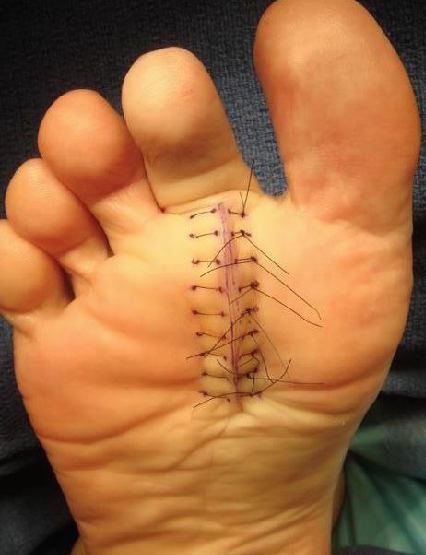

We utilize a linear plantar incision directly under the MPJ, from the edge of the sulcus under the toe to the junction of the arch/weightbearing fat pad. It is helpful to mark the incision as well as the proposed location of each suture prior to making the incision. We use an interrupted vertical mattress suture for closure.

Following repair of the plantar plate, perform final closure using vertical mattress 5/0 nylon or polypropylene sutures to repair the subcutaneous fascia and skin in one step. We avoid placing any absorbable sutures in the deep tissues to reduce foreign body reaction and thereby reducing scarring. Then dress the wounds with multilayered compressive gauze and wraps.

Patients can partially bear weight on the heel of the surgical foot and receive a surgical shoe and crutches/walker/Roll-A-Bout for assistance. Follow up with them at one week for a dressing change and then again at the second week following surgery. At two weeks, remove the plantar sutures and reinforce the wound with tape strips. Discourage the patient from fully bearing weight on the plantar scar until six weeks following surgery. One should also direct the recovery course around other bone procedures. At the six-week visit, the plantar skin will slough the thick epidermal eschar and this will reveal a remarkably supple fine line scar, which will continue to mature for up to a year following surgery.

No procedure is without potential complications. Plantar plate repair is similar in that respect. Under- and overcorrection are possible as is re-dislocation of the chronically dislocated toe. Plantar incision dehiscence or infection is extremely rare but possible. Vascular compromise and loss of a digit is possible but this has not occurred in more than 200 consecutive cases. Persistence of a plantar callus is common but a painful plantar scar is rare. In general, the plantar scar is typically difficult to locate by the one-year mark following surgery and is always more supple than the dorsal scars.